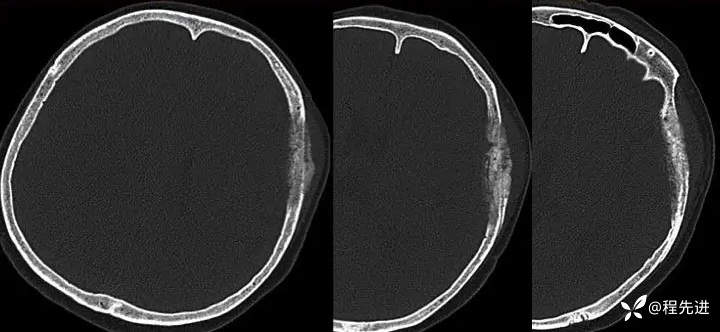

【患者信息】:女,58岁

【现病史及既往史】:发现头皮肿块,进行性增大2年余

【检查】

影像检查: